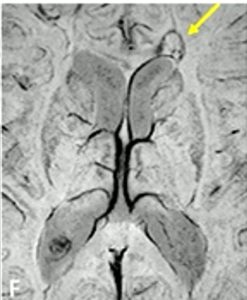

Paramagnetic Rim Lesion (PRL)

Another term that may be unfamiliar is paramagnetic rim lesions, or PRLs (pronounced “pearls”). PRLs are a type of lesion specific to MS. Also known as “chronic active lesions,” PRLs feature a central core of demyelination surrounded by persistently inflamed cells, typically microglia. These microglia may contribute to the gradual expansion of the lesion. They also contain iron, which appears as a rim around the lesion on the same MRI sequence that is used to detect the central vein sign.